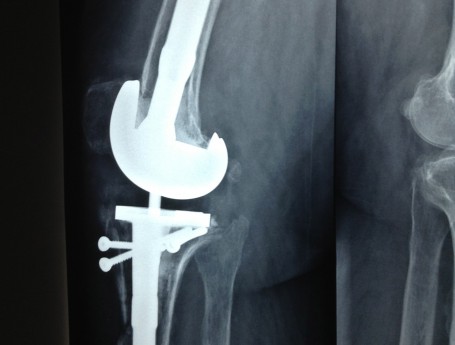

Total Knee Arthroplasty After a non-union

Revision Total Knee Replacement After a fructure

Total Knee Replacement